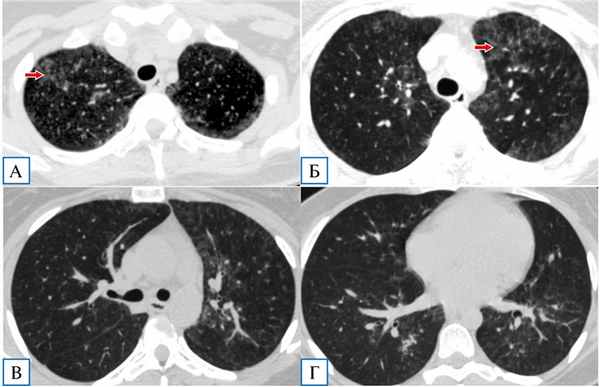

Диагноз коронавирусной инфекции изменен на диагноз пневмоцистной пневмонии на фоне ВИЧ-инфекции, в связи с чем начата терапия ко-тримоксазолом (в дозе 1920 мг внутривенно капельно 4 раза в день), глюкокортикостероидами (метилпреднизолон по 250 мг внутривенно капельно в первые трое суток, далее перорально по 16–12 мг/сут), а также антикоагулянтная, дезинтоксикационная терапия. В течение первых 12 ч от начала терапии отмечалась дальнейшая положительная клиническая динамика в виде полной нормализации температуры тела, регресса дыхательной недостаточности (сатурация О2 на атмосферном воздухе составляла 97%), уменьшения кашля и астении. В дальнейшем отмечено улучшение лабораторных показателей: нормализация уровней лейкоцитов, С-реактивного белка (3,1 мг/л), ИЛ6, прокальцитонина, снижение лимфопении до 7,5% (0,67 в абсолютных значениях). Также была обнаружена положительная КТ-динамика в виде значительного регресса зон «матового стекла» (рис. 2). Пациентка была выписана с рекомендациями продолжения терапии ко-тримоксазолом и метилпреднизолоном перорально еще не менее 2 нед и обращения в СПИД-центр для дальнейшего обследования и назначения антиретровирусной терапии.

Рис. 2. Пациентка Я., 29 лет: контрольная компьютерная томография грудной клетки на 7-й день госпитализации

Примечание. Отмечается существенная положительная динамика: сохраняются отдельные фокусы «матового стекла» преимущественно в верхних долях (А, Б, показаны стрелками), в нижних долях минимальные интерстициальные изменения (В, Г). «Воздушные ловушки» не визуализируются.